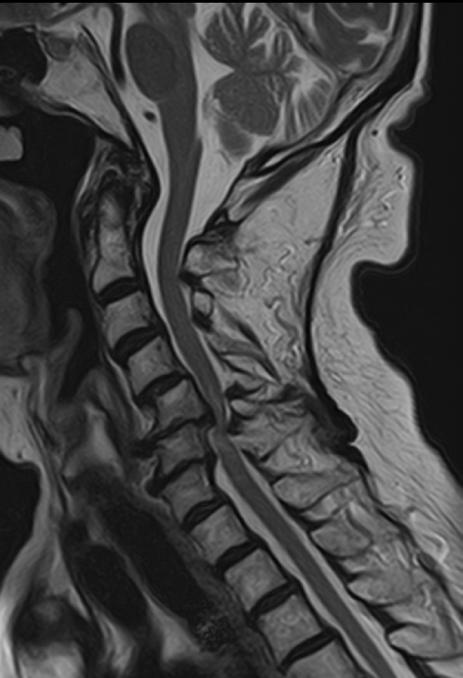

4

Cervical Spine

- Sagital T2

- Resolution: 0.9 x 0.9 mm

- Slice Thickness: 3.0 mm